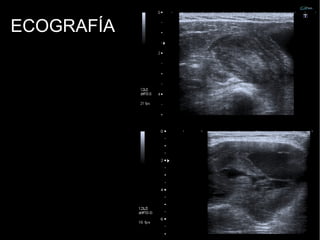

ECOGRAFÍA:

Ecogenicidad mixta.

Heterogeneidad.

Áreas centrales

serpinginosas hipoecoicas.

ECOGRAFÍA

7 cm en diámetro mayor

CC;

Vascularización periférica¿?

ECOGRAFÍA: 7 cm endiámetro mayor CC; Vascularización periférica¿?